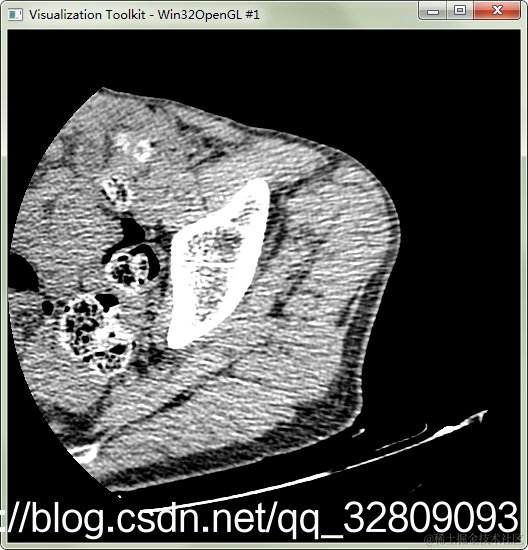

实例14:读取DCM医学图像并显示

在这里插入图片描述

#include "vtkAutoInit.h"

鼠标左键按住不放,上下移动调整窗位,左右移动调整窗宽